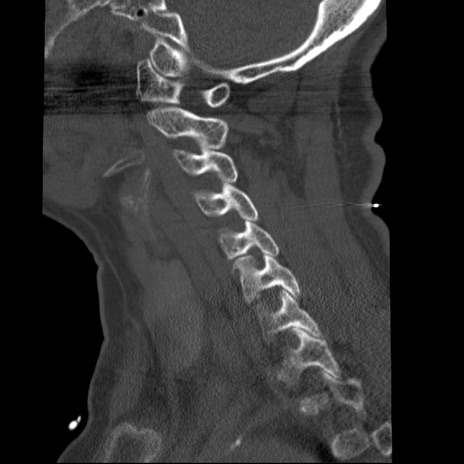

症例50 頚椎CT(矢状断像)

【症例】60歳代女性

【主訴】後頭部〜右後頸部にかけての痛み

【現病歴】本日飲食店でコーヒーを飲んでいたところ、突然後頭部〜右後頸部にかけて痛みが出現し、右上肢の感覚障害を伴ったため救急要請。

【身体所見】脳神経学的に明らかな異常所見を認めず。右上肢に軽度の感覚障害あり。

異常所見と診断は?

頚椎CT